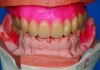

Fig 2. The face collapses inward when the bone and teeth are lost.<

Figure 2

Often when teeth are lost as a result of periodontal disease, tooth decay, or traumatic injury, alveolar bone that houses teeth is lost. Particularly in the maxillary arch, bone loss moves the bony scaffolding supporting the facial muscles medially, posteriorly, and superiorly, causing loss of lip support and eversion. Figure 1 and Figure 2 illustrate the inward collapse of the face when the bone and teeth are lost.